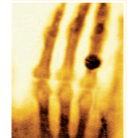

Wilhelm Roentgen's X-ray photograph of his wife's hand

Wilhelm Roentgen